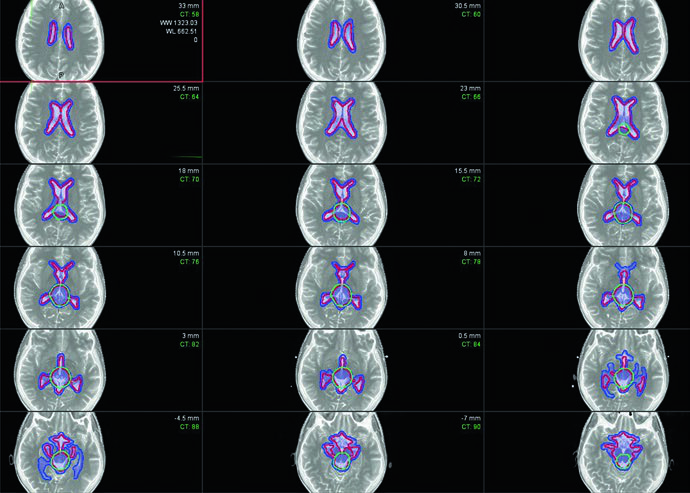

Volúmenes blanco para irradiación craneoespinal

El contorneo debe realizarse corte por corte en la TC de planificación. Las tablas siguientes resumen las definiciones recomendadas.

| CTVCSI | Todo el volumen contenido por la duramadre en contacto con el líquido cefalorraquídeo, incluido el pseudomeningocele posoperatorio. En niños en crecimiento, incluye el cuerpo vertebral completo y el canal; en individuos adultos, solo el canal. |

| PTVCSI | CTVCSI + 3 a 10 mm según la confianza en el posicionamiento diario y la experiencia institucional. |